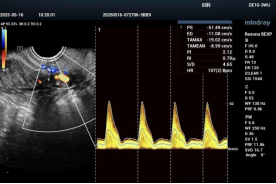

无论是正在备孕,还是已经成为准妈妈,子宫动脉超声检查能帮助发现潜在问题,真正做到“早知道、早安心”!

怀孕就像给“宝宝盖房子”,子宫血流就是输送营养和氧气的“补给线”。如果血流不畅,阻力太高,宝宝可能吸收不到足够的营养,容易发生胎停、发育迟缓甚至流产。这项检查能在早期发现问题,让医生和妈妈有机会提前干预,守住宝宝健康成长的第一关。

三、检查过程是怎样的?

它和普通的B超差不多,受检者只需要躺在检查床上,医生会用一个小小的探头在腹部轻轻移动(孕早期可能会用经阴道探头,更精准哦),几分钟就能完成!